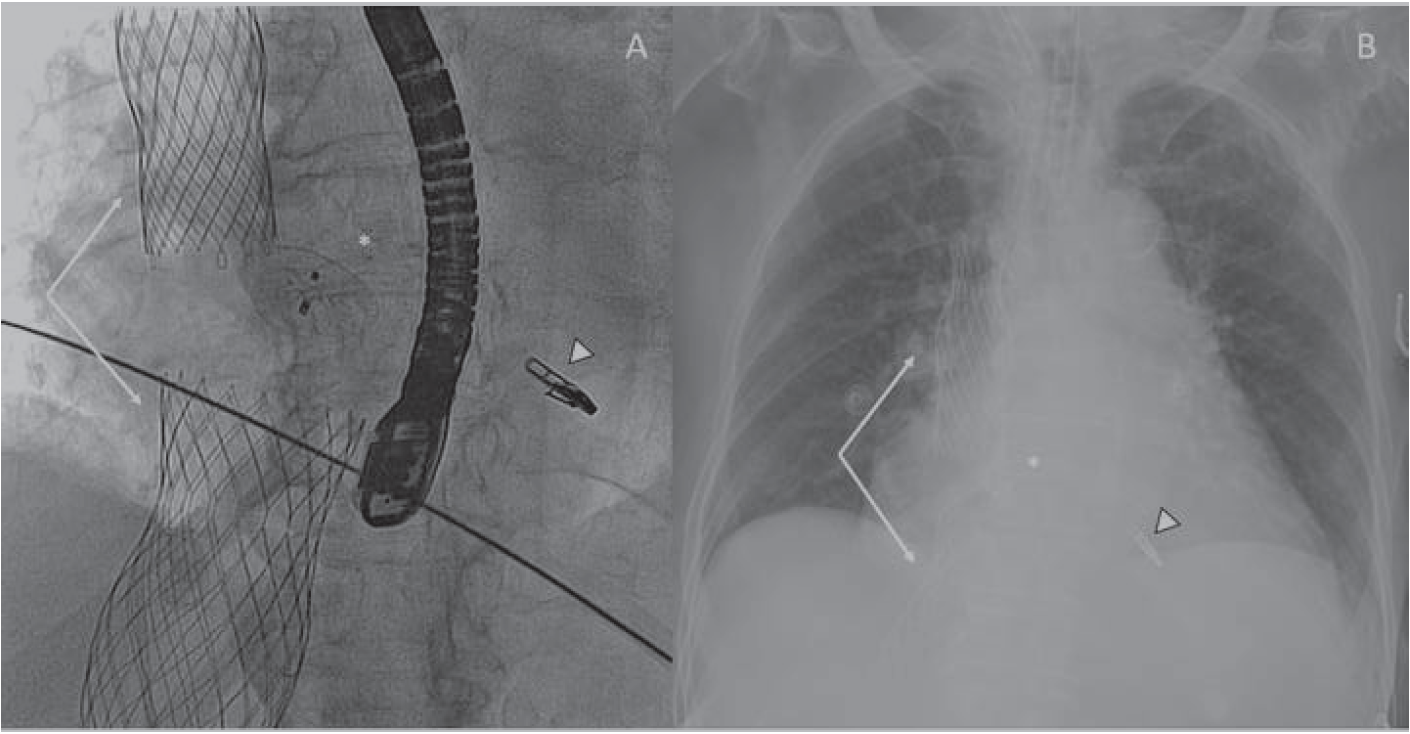

Six months later, the patient continued with right heart failure. Right heart catheterization revealed a mean pulmonary artery pressure of 34 mm Hg and a right atrial pressure of 21 mm Hg (V-wave of 30). An interventional heterotopic tricuspid valve implantation was planned based on computed tomography (Figures 2B, 2C). Two TricValve self-expanding biological valves (P+F) were successfully implanted percutaneously (Figures 2D, 2E; Video Series).

To the best of our knowledge, this case represents the first patient with Mitraclip, Amplatzer, and TricValve devices (Figures 3A, 3B) with a profound clinical improvement and a long-term follow-up, and illustrates how the treatment of high-risk patients with polyvalvular disease has changed in the last few years.